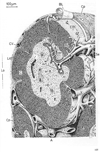

小動脈;細動脈Arteriole; Small artery(Arteriola)

小動脈;細動脈【しょうどうみゃく;さいどうみゃく】 Small artery immediately preceding a capillary.(小動脈はわずか1-2層の平滑筋層のみからなる中層(筋層)をもつ細い動脈。毛細血管網に連続する直前の終動脈。)